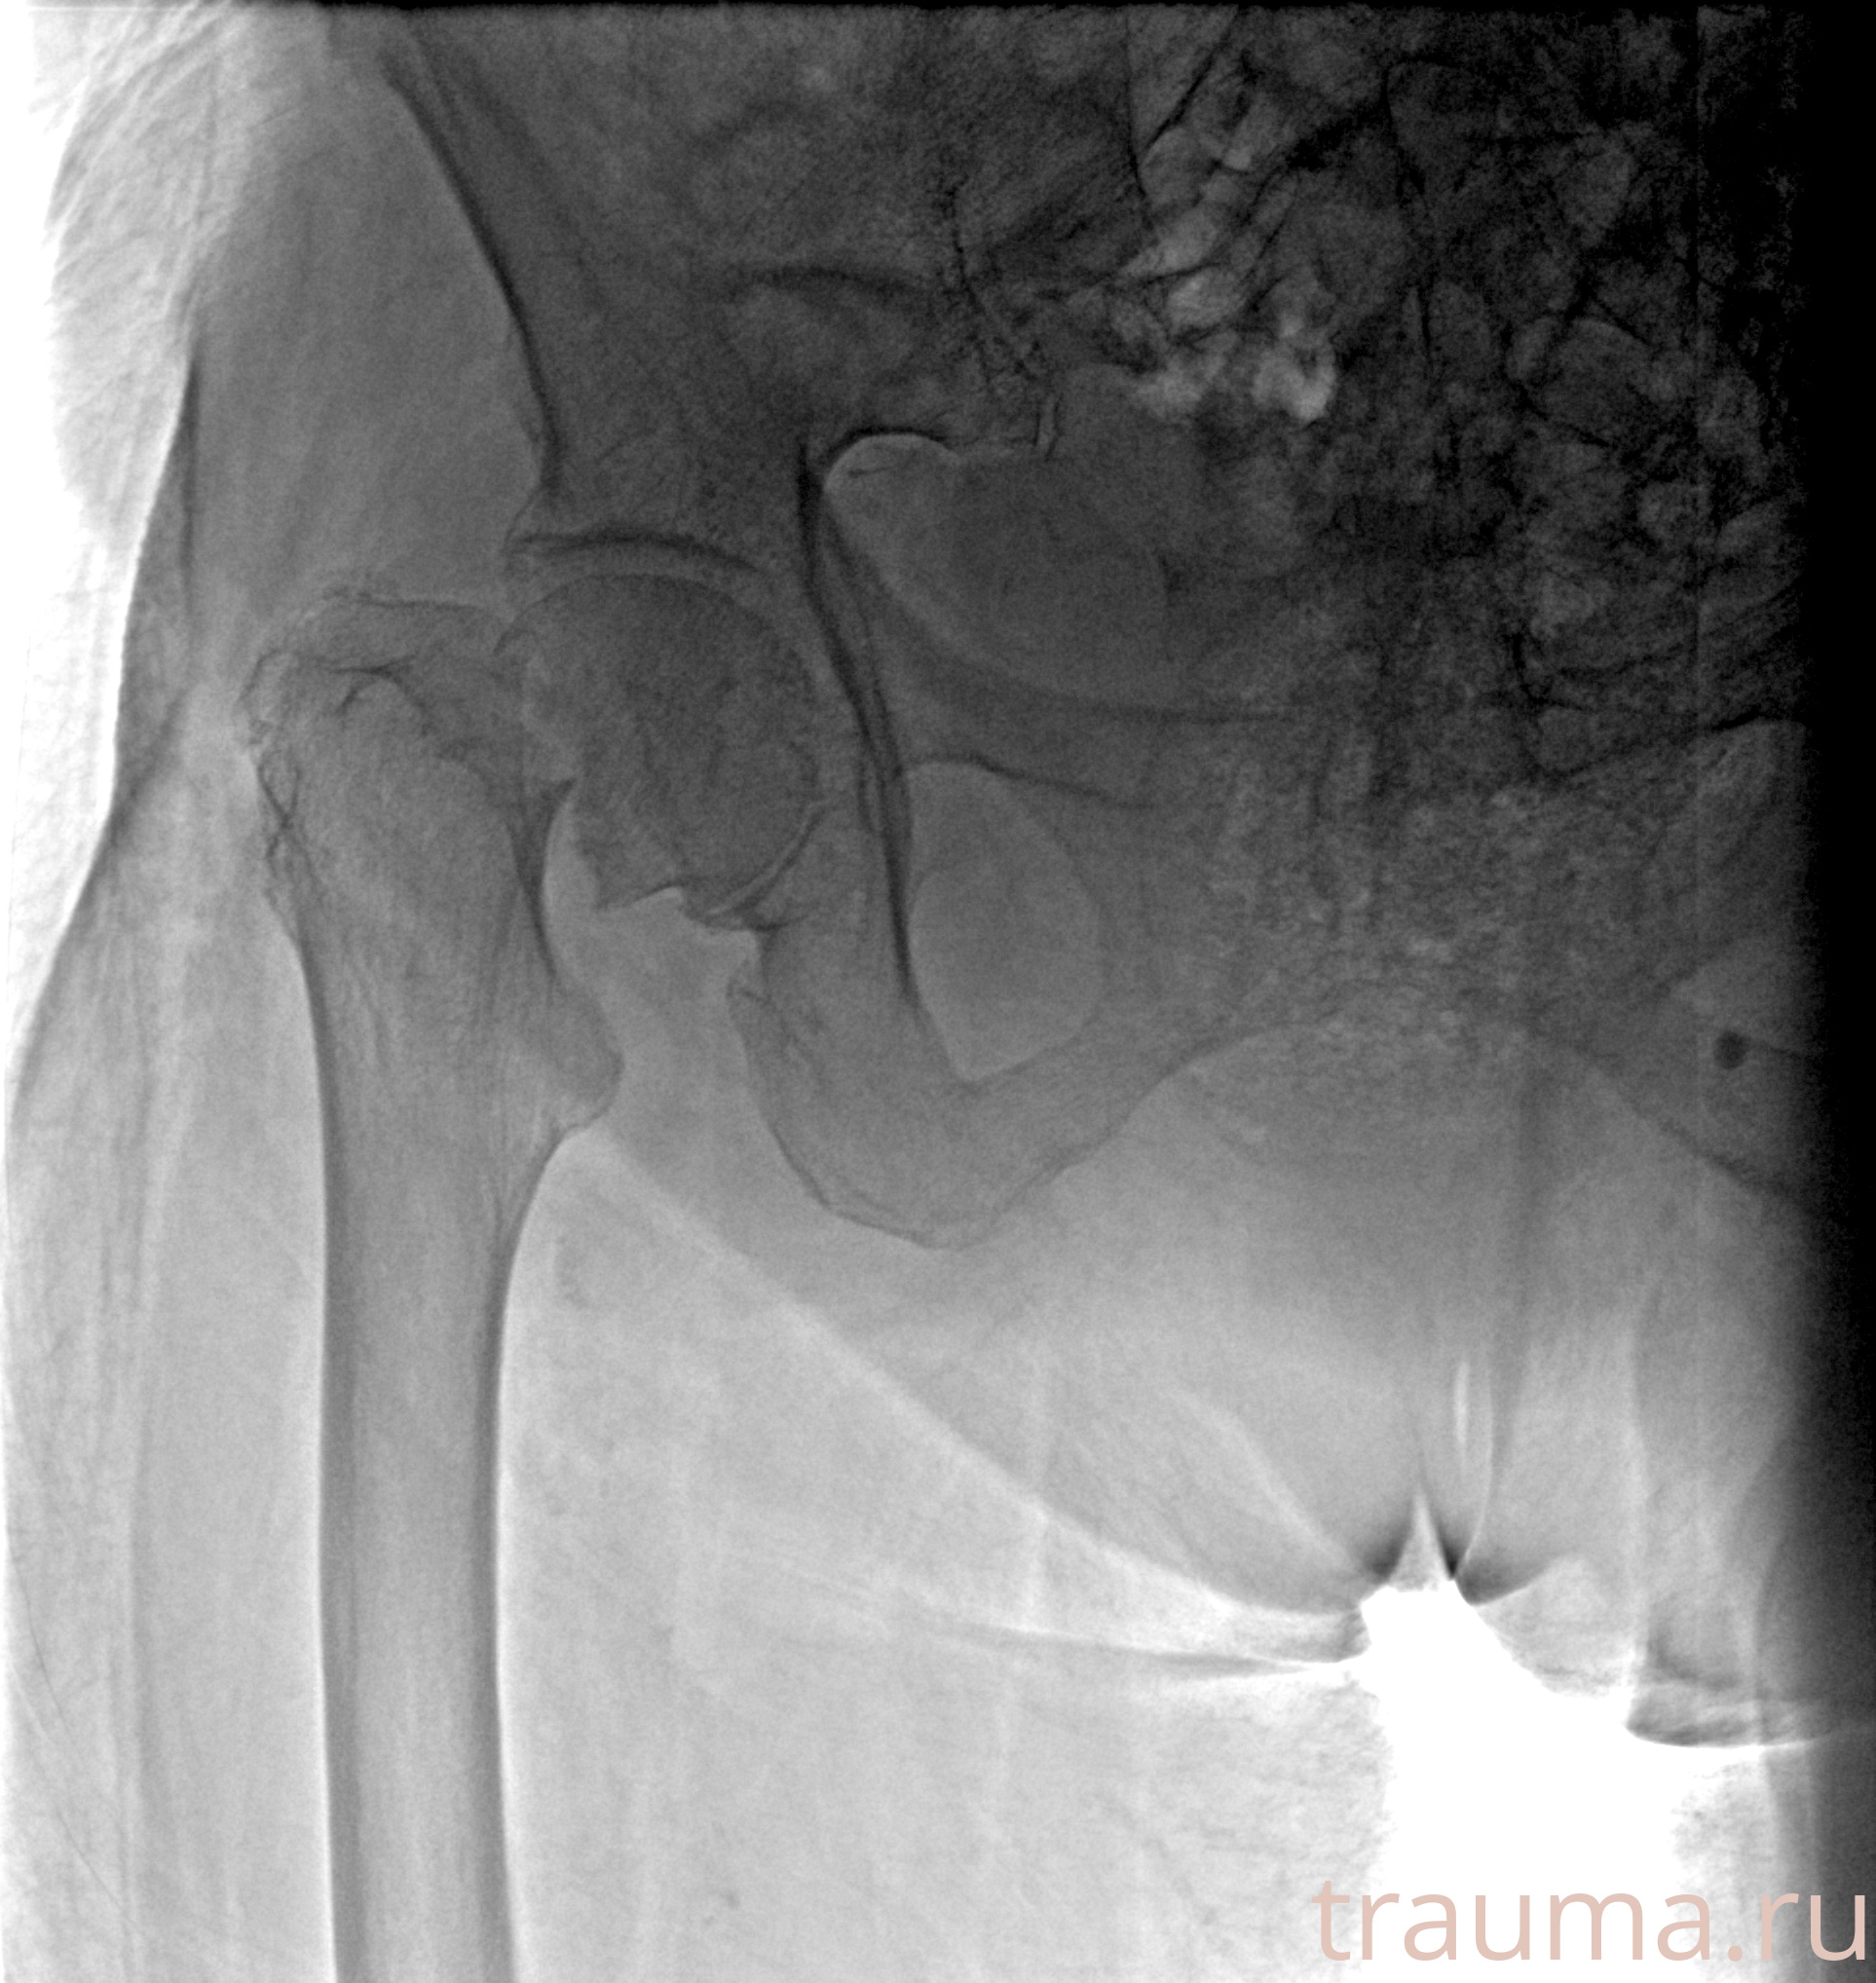

Рентгенограммы

Рентген на дому: по вашему адресу приезжает врач-рентгенолог, травматолог-ортопед с мобильным рентгеновским аппаратом, проводит диагностику травмы или заболевания, делает необходимые рентгенограммы, дает рекомендации по дальнейшему лечению. Получить качественные снимки в домашних условиях возможно благодаря уникальной методике, разработанной МосРентген Центром для института  Склифосовского